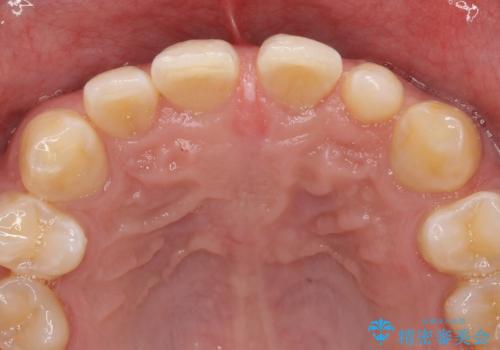

- 上顎前歯のすきっ歯が気になるといらっしゃった方の症例です。

上顎前歯のみの治療を希望されたので、部分矯正を行いました。

左上2の矮小歯はオールセラミッククラウンによる補綴を行いました。

今回用いたオールセラミッククラウンは、ジルコニアフレームという白い素材の上にセラミックを盛っているため審美性が非常に高いのが特徴です。

またジルコニアは人工ダイヤモンドの材料にも使われているほど高い強度を持っており、そのためオールセラミッククラウンは審美性だけでなく、奥歯やブリッジの補綴も可能とするクラウンです。